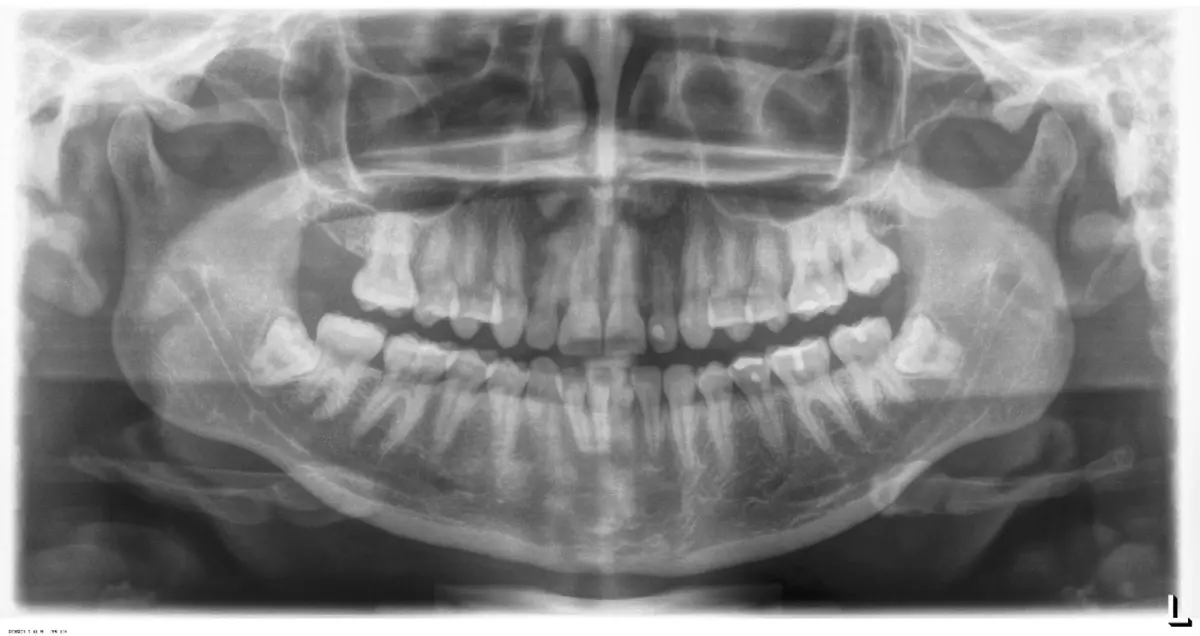

Es imprescindible conocer la ubicación de la tercera molar. Se puede emplear, adicionalmente a la evaluación clínica, herramientas radiográficas (panorámica y periapical) y tomográficas (Cone beam) para determinar la posición, grado de retención y proximidad a estructuras vecinas de riesgo como el nervio dentario inferior y así evitar lesiones (Figura 1).

El procedimiento se inicia colocando anestesia troncular para bloqueo del nervio dentario inferior y sus ramas. Luego, se establecerá el diseño de acceso según la disposición de la molar a extraer. Para fines didácticos, se explicará cómo se realizaría la extracción de la molar de la Figura 1: se realiza una incisión horizontal a nivel de la zona retromolar hasta llegar a distal de la segunda molar, continuándose con una incisión intrasurcular hasta mesial de la segunda molar, finalizando con una incisión vertical a espesor total hasta llegar a la línea mucogingival (Figura 2).